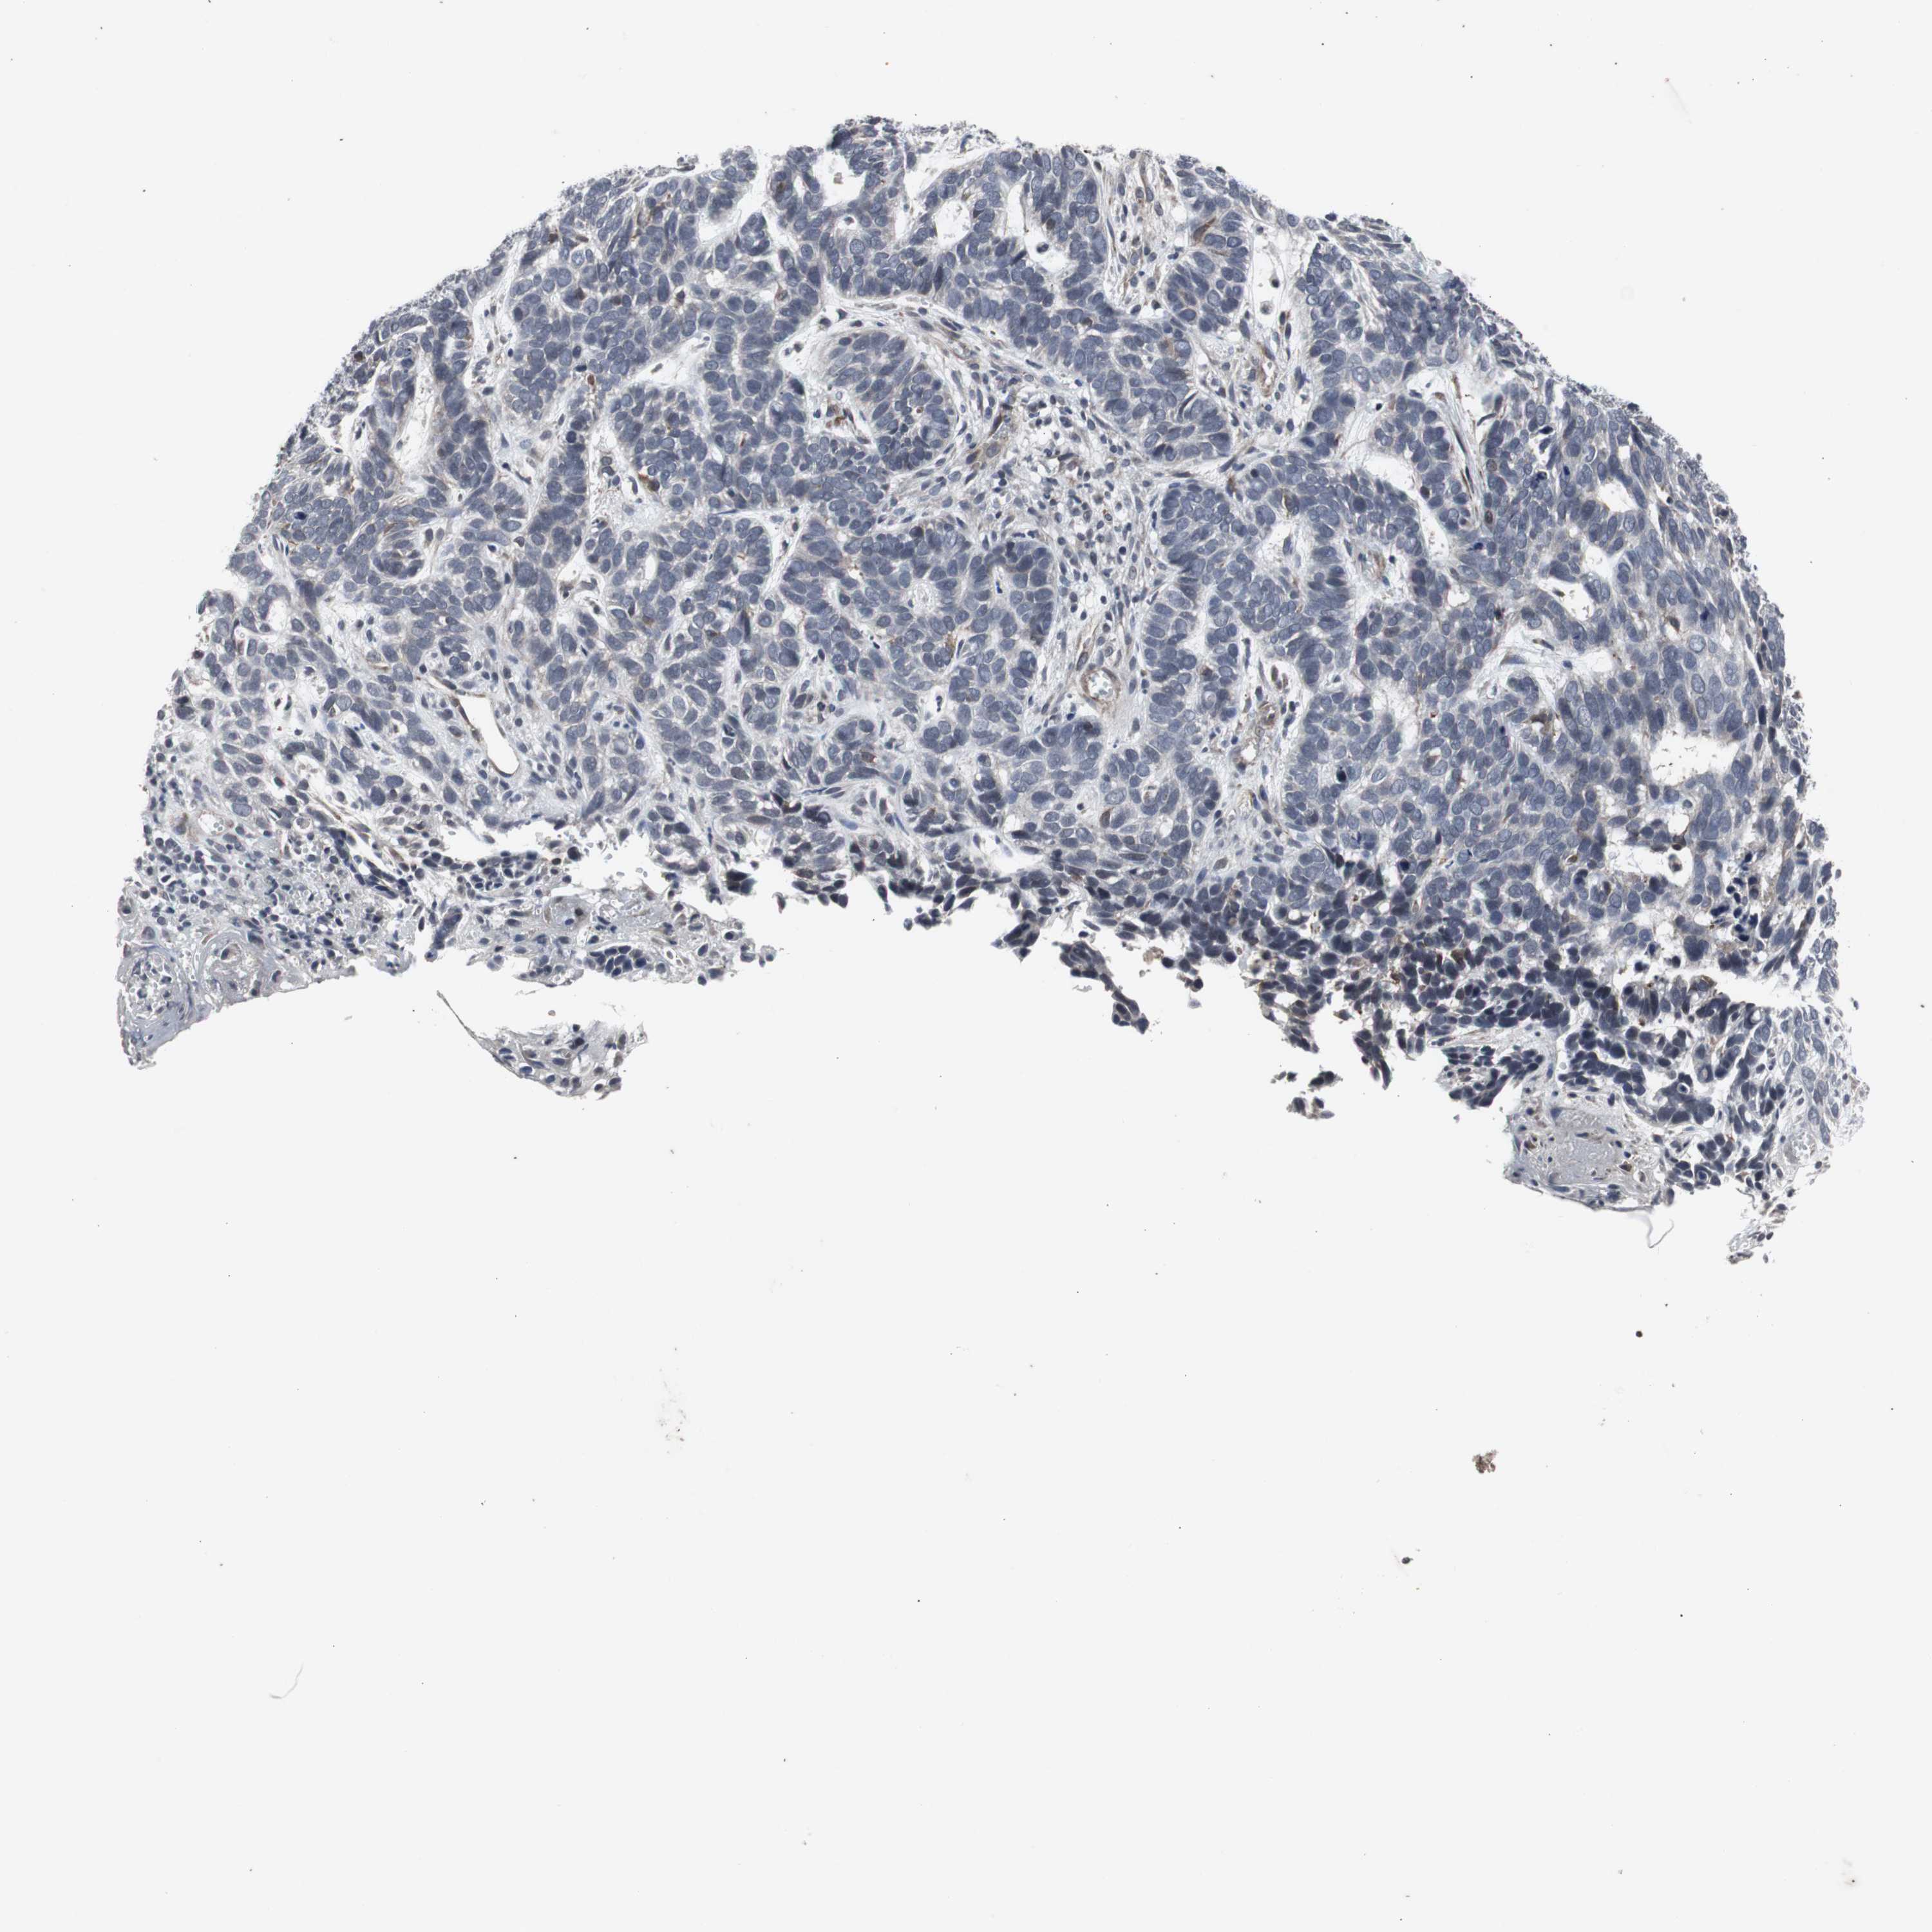

Antibody CAB005337

Staining

High

Medium

Low

Not detected

Intensity

Strong

Moderate

Weak

Negative

Quantity

>75%

75%-25%

<25%

None

Location

Nuclear

Cytoplasmic/membranous

Cytoplasmic/membranous,nuclear

Squamous cell carcinoma, NOS

Squamous cell carcinoma, metastatic, NOS

Basal cell carcinoma

Papilloma, NOS